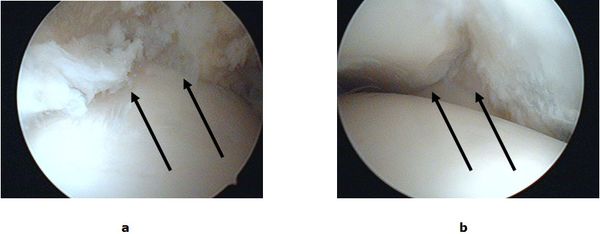

Bei Schmerzen auf Grund von Narbenbildungen und Einklemmungen von Gelenkkapsel und Schleimhaut (meniskoides Syndrom, Impingement) ist die Gelenkspiegelung die Therapie der Wahl. Ein minimalinvasives Verfahren bei dem durch zwei kleine Schnitte (kleiner 1cm) nahezu das ganze Gelenk eingesehen werden kann. Während der Spiegelung wird mit speziell geformten Feininstrumenten das krankhaft veränderte Gewebe entfernt und die Einklemmung beseitigt.

Abb.2: a Eingeklemmtes Narbengewebe im Gelenkspalt. b Freie Einsicht in den Gelenkspalt nach Entfernung des Narbengewebes.